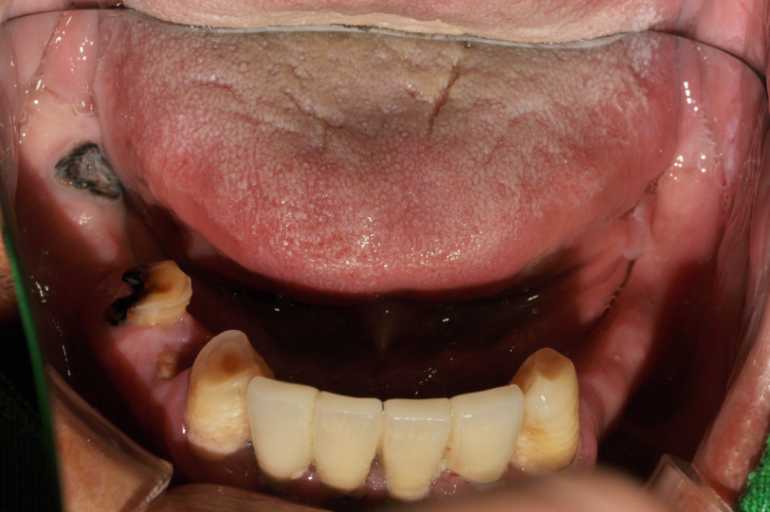

고정형 무치악 임플란트 전후 사례

무치악 임플란트 전후 실제 사례 #1, #2

이미지 위에 가운데 동그라미를 클릭한 상태에서 왼쪽 또는 오른쪽으로 드래그해보세요! 드래그할 때마다 환자의 전후 변화를 확인하실 수 있습니다.

#무치악 임플란트 환자 사례 : 임플란트로 찾은 새로운 미소